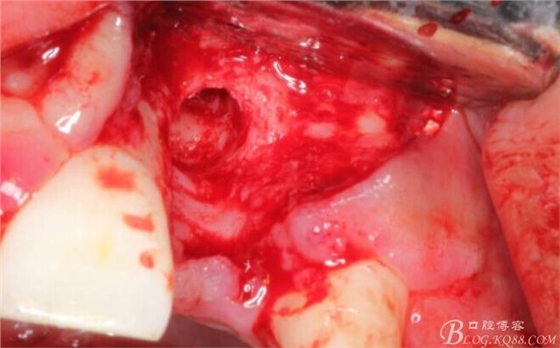

于是我果斷告知患者,手術(shù)失敗了,不能拖延,如不及時處理,炎癥繼續(xù)發(fā)展會很快波及鄰牙牙槽骨。患者接受我的建議。切開翻瓣,骨粉及生物膜消失了,骨吸收嚴(yán)重,幸運的是,因為處理及時,鄰牙骨支持依然存在。

徹底掻刮。